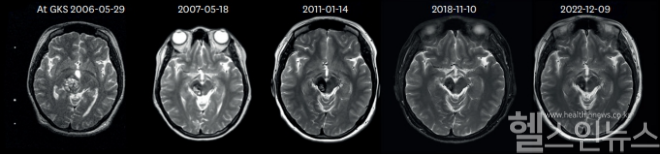

이에 서울대병원 신경외과 백선하 교수팀(명호성 임상강사)은 1998년부터 2012년까지 감마나이프 방사선 수술을 받은 뇌 해면상 혈관종 환자 233명 중 10년 이상 추적 관찰이 가능한 79명의 환자(96개의 병변)를 대상으로 장기 예후를 분석한 연구 결과를 26일 발표했다.

연구 결과, 10년 이상 추적 관찰된 79명의 환자군(GKS(S))에서 감마나이프 수술 전 출혈률이 21.4%였던 환자들은 수술 후 2년 차에 3.8%, 10년 차에 1.4%로 크게 감소했으며, 그 이후에는 2.3%로 유지됐다. 특히 뇌간에 위치한 해면상 혈관종 환자의 경우, 수술 전 출혈률이 27.2%였으나 수술 후 2년 차에는 6.0%, 10년 차에는 3.5%로 감소하여 출혈 위험이 크게 줄어들었다.